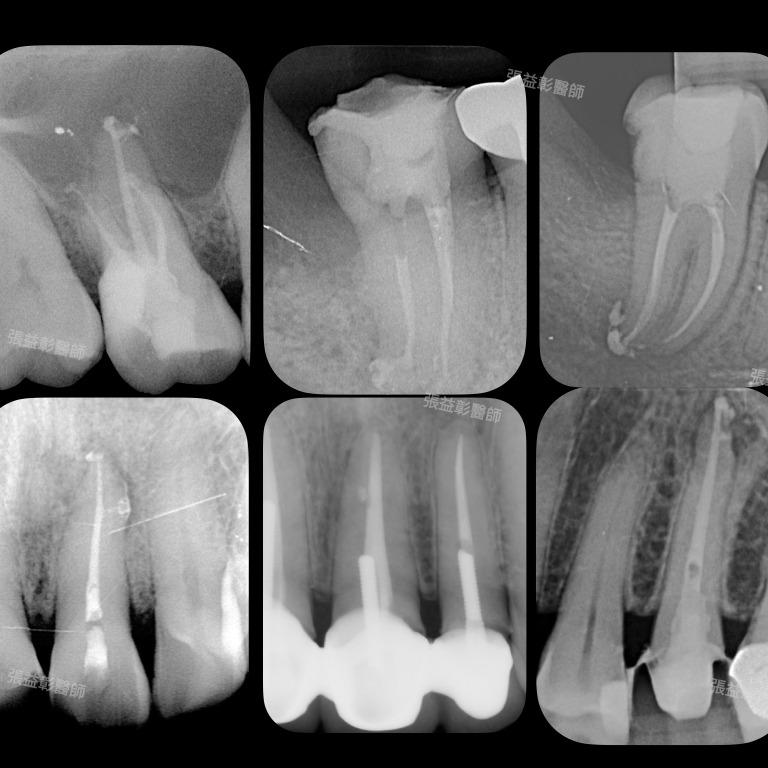

張益彰醫師 | 衛福部定牙髓病專科

多根管小臼齒

側根管